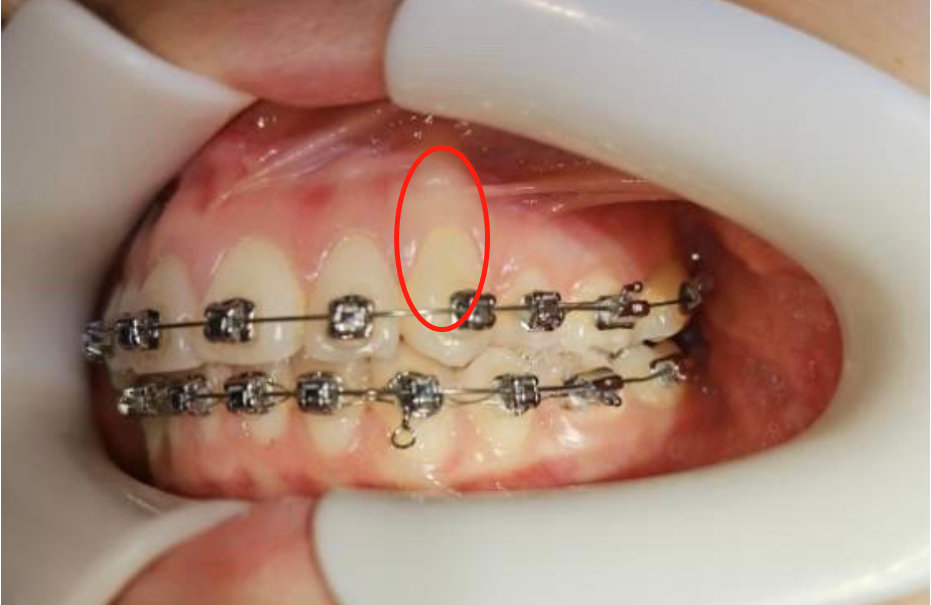

骨开窗是因为牙槽骨缺损,导致牙根没有得到完整覆盖,或者因为正畸施力不当等原因,导致部分牙根在牙槽骨,甚至牙龈上开了个窗口一样暴露出来,肉眼能见到牙龈根部露白。

我们判断骨开窗和骨开裂最直接的办法就是肉眼观察,,正畸医生则会通过CBCT测量数据来精确测量,自己实在判断不准的小伙伴,可以去正规的牙科诊所做检查,或者把照片发给小优医生,让我来帮你判断。 这里要特别说明一点的是,用窗和门来形容骨开窗和骨开裂,并不代表骨开裂就一定要比骨开窗更严重,毕竟窗可以是大落地窗,门也可以是很小的门。